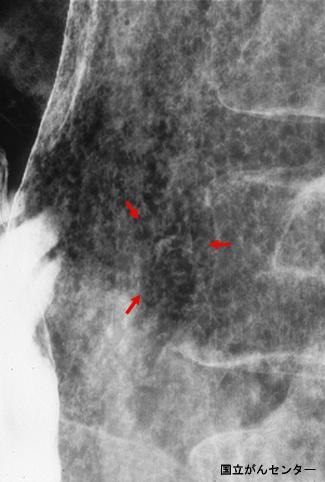

疾患(病理主体)の分類悪性上皮性腫瘍/腺癌

部位(臓器別)胃(部位)/体部

検査方法X-P

腫瘍の肉眼分類0型(表在型)/IIc型(IIc)

病変の最大径(ミリ)1〜9

腫瘍の深達度m